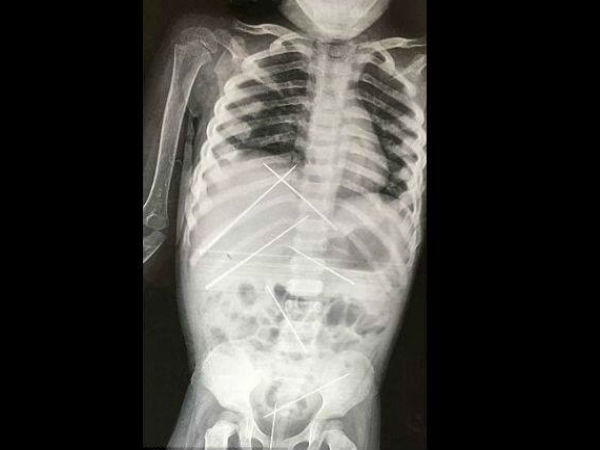

Needles Were Found Inside A Girl’s Body After Horrific 'Black Magic' Abuse

This is a very disheartening story of a small girl who was used as a Voodoo doll. Find out how.

A 3-year-old kid was admitted in the hospital after her mother found out that her boss had inserted needles inside the body of her little daughter and used her as a Voodoo doll.

Doctors said they extracted seven four-inch needles from her, including her private parts. While two needles were found inside her liver and urinary bladder, one each was found in her kidney, vagina and lower abdomen.